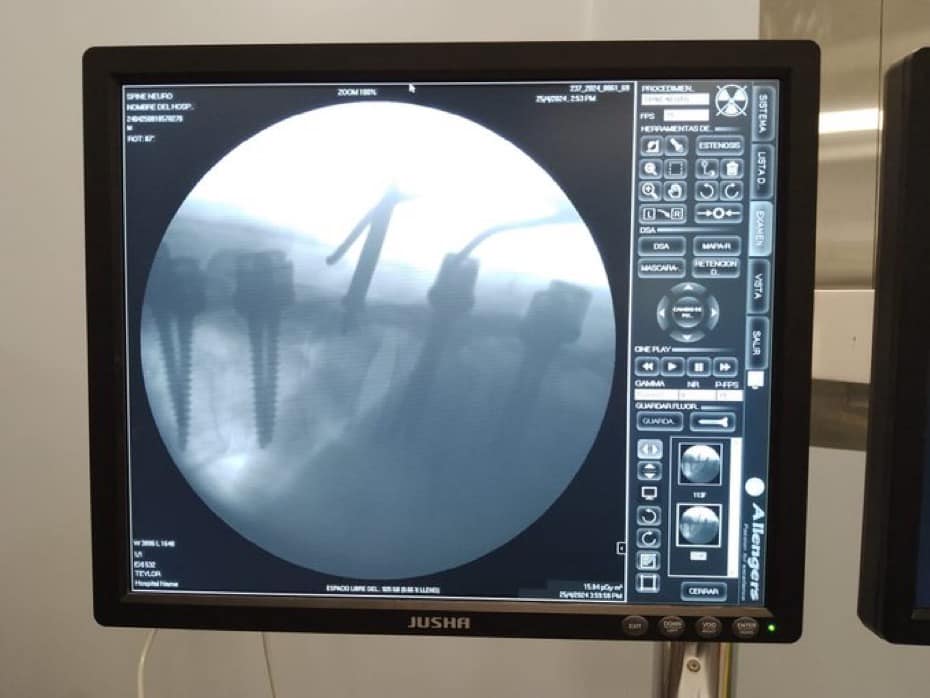

El equipo médico realizó una laminectomía T10 y T11, junto con una duroplastia con parche de fascia y una corpectomía de Smith-Patterson de sustracción pedicular.

Se colocaron:

-ocho tornillos

-dos barras

-un conector transverso

Para garantizar la estabilidad. La cirugía duró 8 horas y fue todo un desafío, pero gracias al profesionalismo del equipo, el paciente está en proceso de recuperación y regresará a casa el próximo viernes.